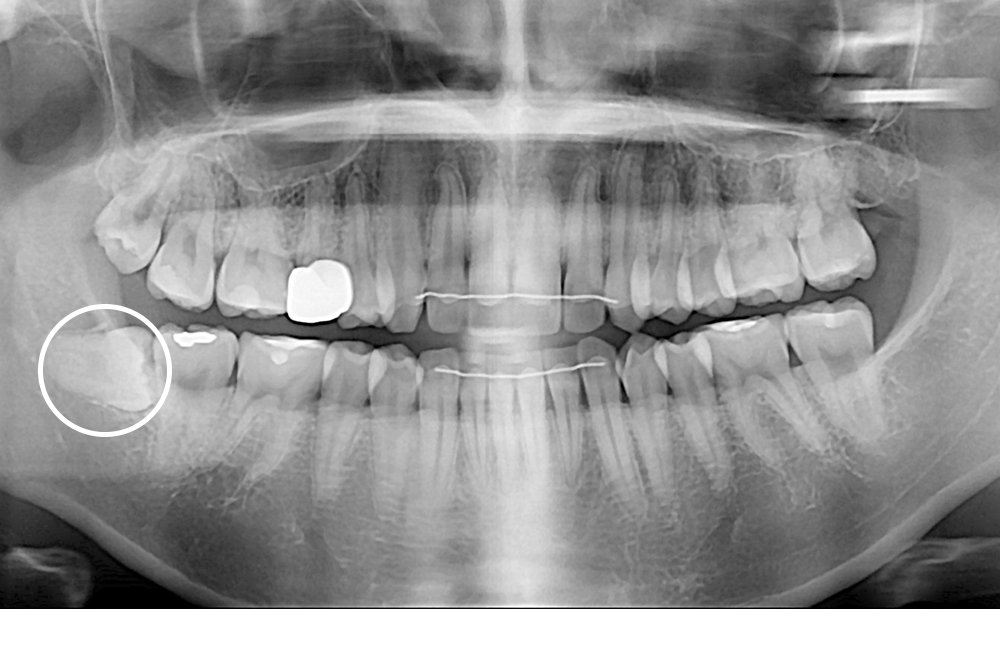

[사랑니] 매복 사랑니 발치

치료전 : 2018-01-09